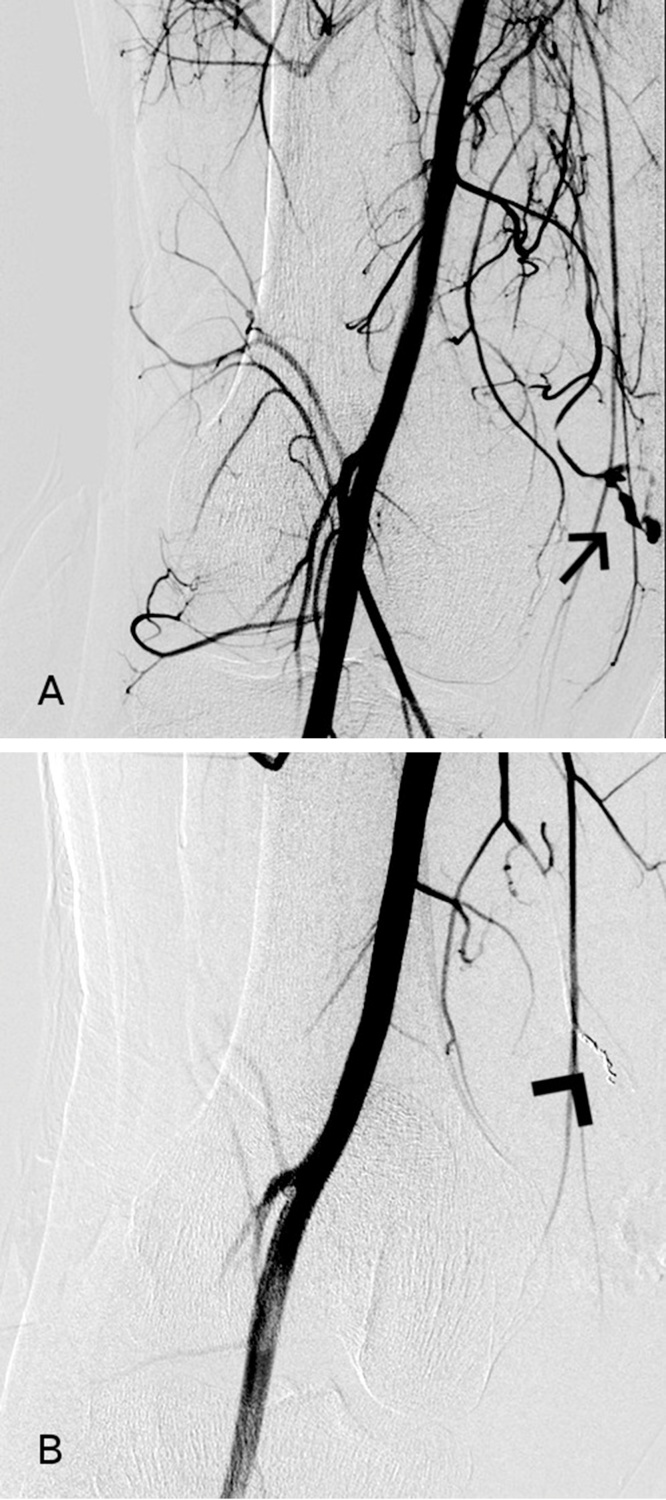

Fig. 2.

Selective angiography. Pre-embolization angiography (A) showing contrast medium extravasation from a distal branch of the DGA (arrow). Post-embolization angiography (B) demonstrating no residual bleeding from the injured vessel (arrowhead).